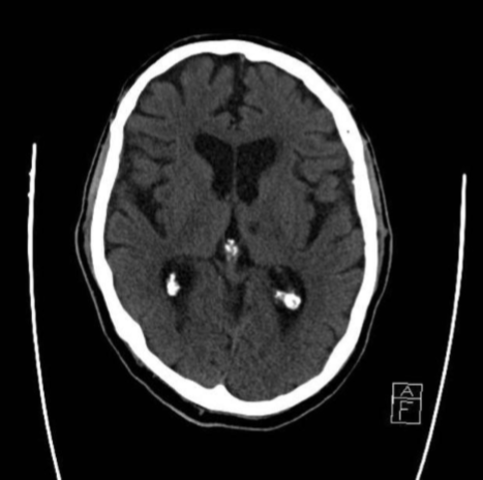

• Tomografía

Tomografía